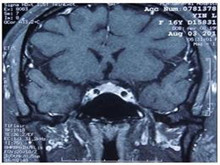

- 异位ACTH综合征的临床检查手段

- 异位ACTH综合征应该做哪些检查?

- 肾上腺疾病应该做哪些检查?

- 肾上腺疾病检查方法有什么